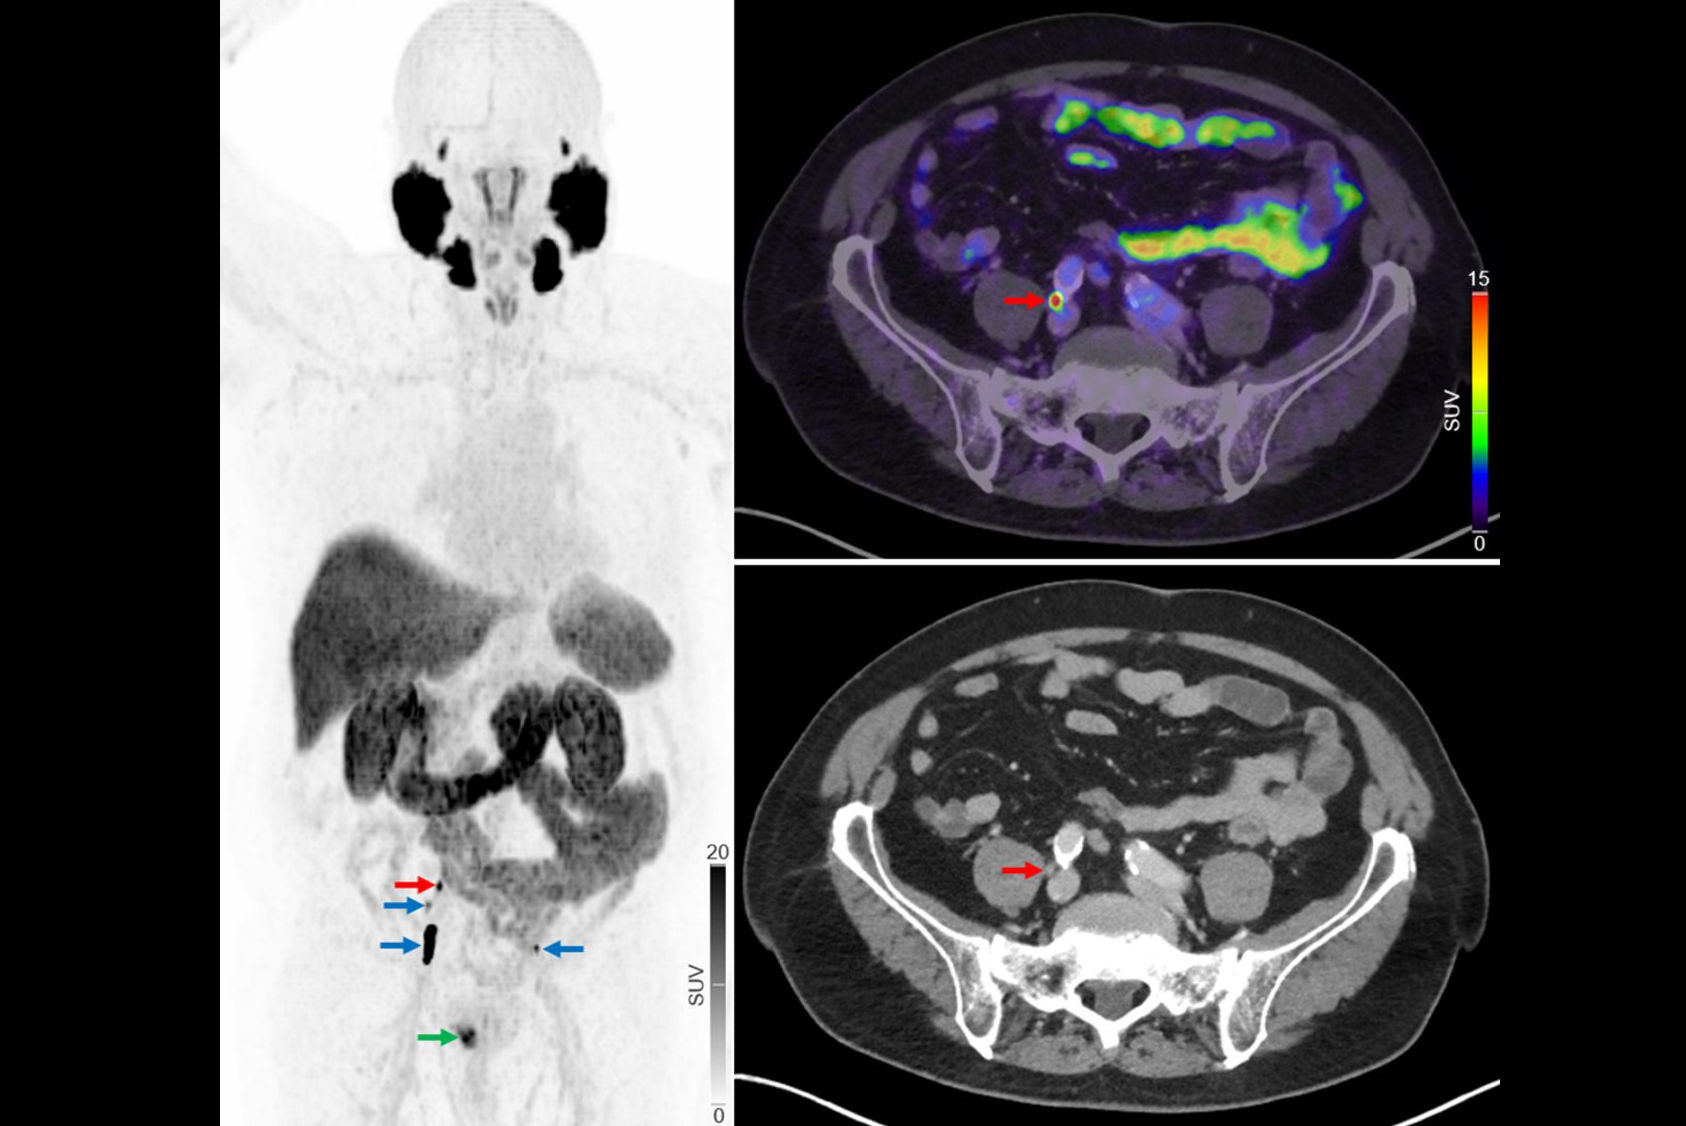

F-18 sodium fluoride (NaF) PET/CT may be a valuable tool for imaging patients with psoriatic arthritis (PsA), as it reveals new bone formation in peripheral joints missed on clinical evaluation, according to a Dutch group.

"F-18 NaF PET/CT may be a novel clinically valuable tool to detect whole-body disease activity of PsA reflected by new bone formation in all disease domains of PsA, depicted in one scan," a team led by doctoral candidate Jerney de Jongh wrote. The study was published November 12 in the European Journal of Nuclear Medicine and Molecular Imaging.

In this study, the researchers enrolled 16 patients with a clinical diagnosis of psoriatic arthritis from a rheumatology center at Amsterdam UMC. Patients underwent whole-body PET/CT scans 45 minutes after injection with F-18 NaF, a radiotracer that can identify new bone formation based on osteoblastic activity.

According to the study results, 81.8% of PET-positive joints were missed on clinical assessment. The team found that only 18.2% of PET-positive joints were clinically positive (that is, tender or swollen). But most PET-negative sites were also clinically negative (611/638). Similar results were found for entheses, with 70.5% of the PET-positive entheses missed on clinical evaluation and 29.5% of PET-positive entheses clinically identified.